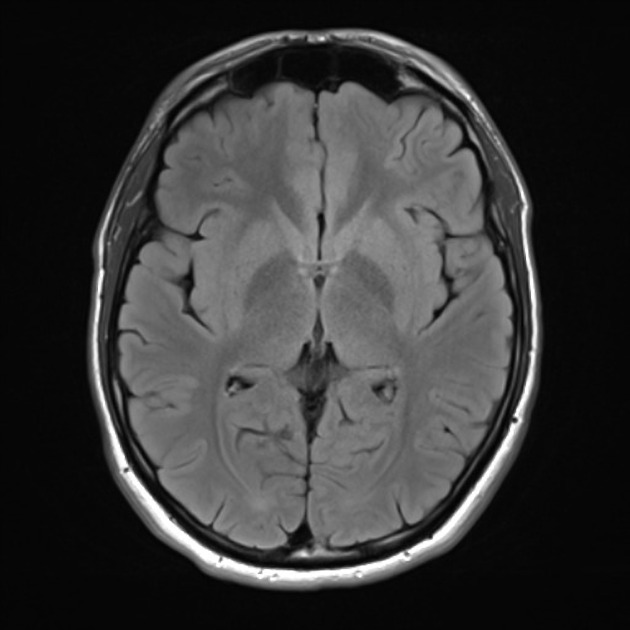

Glioma

Glioma

Glioma

Glioma